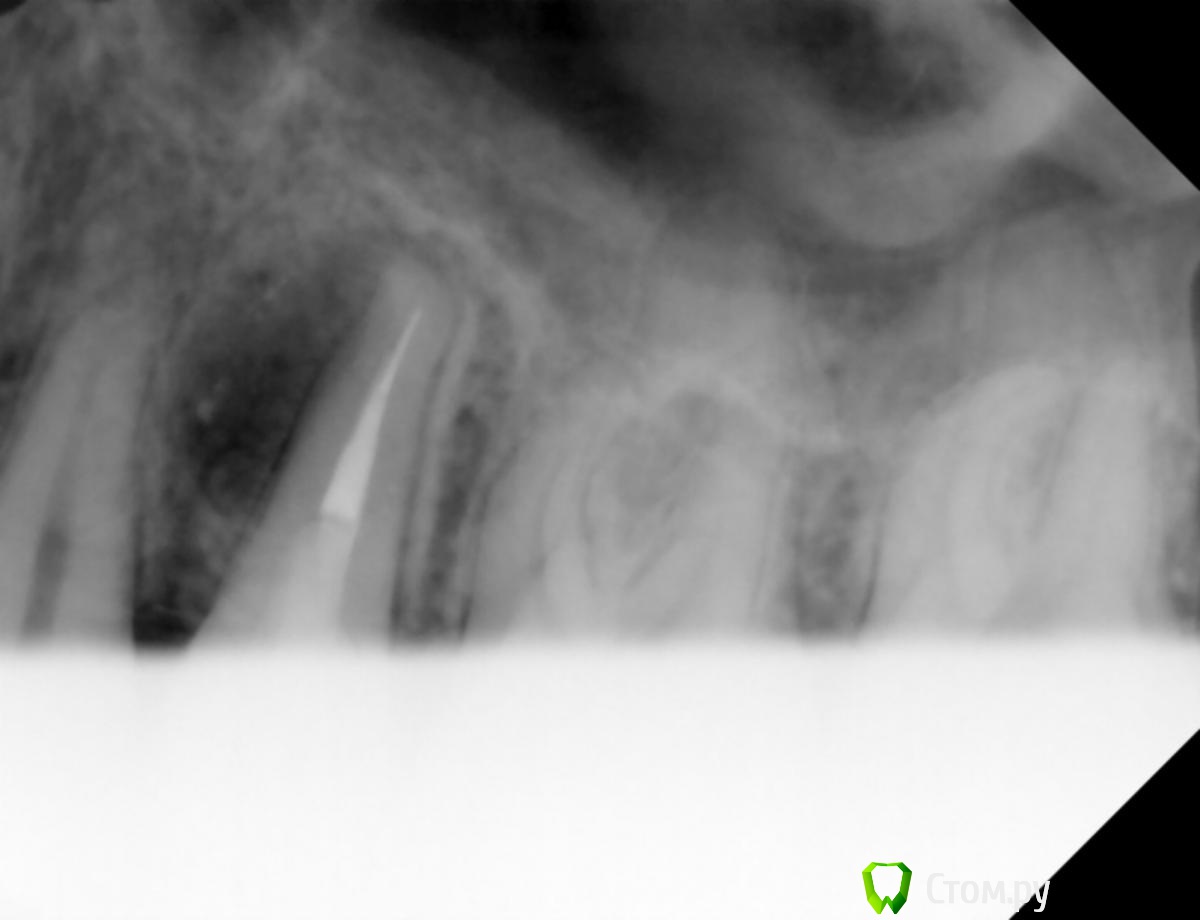

Юлия Арт Опубликовано 14 марта, 2014 Поделиться Опубликовано 14 марта, 2014 (изменено) День добрый, уважаемые специалисты!Месяц назад у верхней 5-ки обнаружили воспаление, врач сказал зуб удалять так она вбоку и ,по его мнению, в канале трещина.Вчера хирург сделал панорамный снимок, и отказался удалять зуб, сказав что нет причины... Сегодня пошла к нему опять-сделали маленькое фото того зуба, воспаление меньше стало, но что дальше делать? посоветуйте, пожалуйста. Можно ли пока оставить этот зуб в покое, надо другими 5-ю штуками заниматься, которые болят сильно. 2 снимка, один сделан в феврале. второй-сегодня, март Изменено 14 марта, 2014 пользователем Юлия Арт Ссылка на комментарий

red_butler Опубликовано 14 марта, 2014 Поделиться Опубликовано 14 марта, 2014 Не дублируйте темы. проблема есть и очаг меньше не стал, просто другой ракурс. Для того что бы понять причину нужна Кт. Я бы такой зуб убрал Ссылка на комментарий